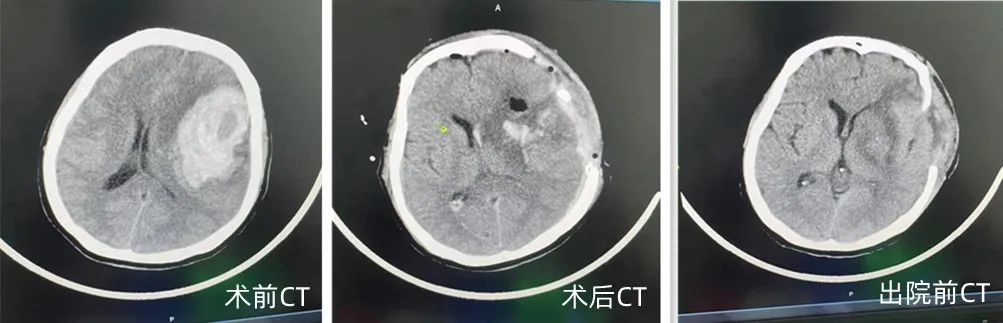

2022年7月28日夜,我们的母亲突发脑出血,我们四个子女将母亲送至辽阳二院,入院时已完全丧失意识,双侧瞳孔放大,呼吸微弱。经检查母亲颅内左侧额颞顶叶有大量出血,出血量约为80mL,且已形成脑疝,病况十分凶险,随后马上被收入至七楼神经外科病房,已经深夜,主治医师魏庆生接待了我们,火速为我们的母亲安排检查,详细的向我们家属介绍病情,然后亲自为我们的母亲实施了手术治疗。

早上7:23分手术室的大门打开了,我们被告知手术很成功,我们接回了有心跳、有呼吸、有温度的母亲,是魏庆生医生,用他高超的医术历经4个多小时的努力救治挽救了我们的母亲,从鬼门关为我们抢回了母亲的生命。术后我们母亲被安排进了监护病房,由于母亲并未脱离生命危险,郝琨主任、魏庆生医生每日细心观察询问病情,关注我们母亲各项生命体征的变化,及时准确安排调整当下病情所需治疗方案,处理各种问题,悉心为我们家属讲解病情,叮嘱注意事项。

此等仁心仁术之仁医怎能不让人为之动容。现在我们的母亲已经出院了,正在接受康复治疗,病情日见好转,期待在不远的将来母亲能站起来亲自向你们感谢救命之恩,我们家属再一次深深的感谢你们,并祝愿你们好人一生平安!!!